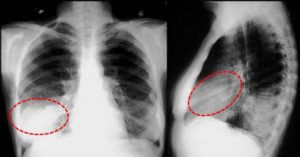

Возможные осложнения туберкулеза и пневмонии

Плеврит, пневмоторакс – наиболее распространенное осложнение, вызванное туберкулезом или пневмонией. В первом случае воспаляется пленка, покрывающая внутренние полости грудной клетки и легкие – плевра. Под ней скапливаются жидкость, гной и кровь.

Во втором случае происходит разрыв полостей в легких и кровоизлияние. Если пациенту немедленно не оказать помощь, может наступить смерть от удушья. Абсцессы легких возможны как при пневмонии, так и при кавернозной форме туберкулеза.

В легких образуются полости с гноем, требующие оперативного лечения.